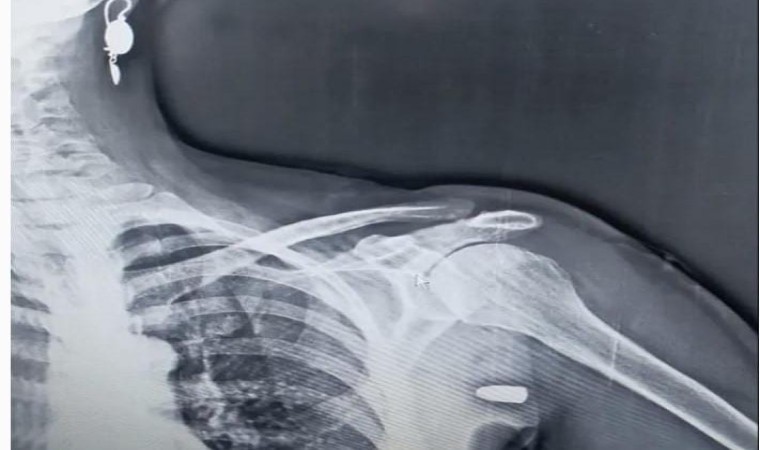

Trabzon’un Tonya ilçesinin Karaağaç Mahallesi yakınlarındaki Hırsafa Yaylası’nda 2022 yılının Kasım ayında ot biçen Asiye İnce (59), sol omuz bölgesinden giren yorgun mermi ile yaralandı. Hastanede tedavi altına alınan İnce mermi çekirdeği ameliyatla çıkartılması sonucu sağlığına kavuştu.